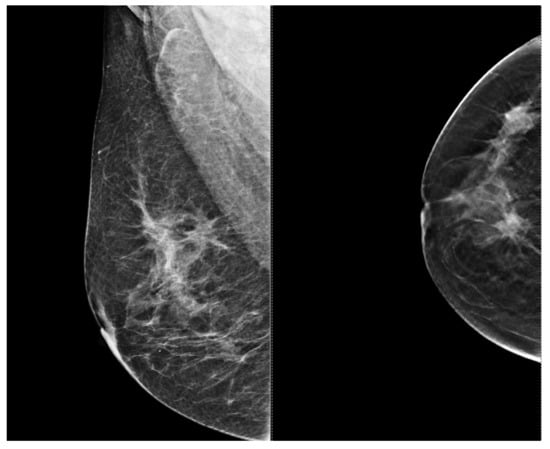

5.3. Low Ability to Detect Microcalcifications

6.4. Supplementary Imaging in Challenging Cases